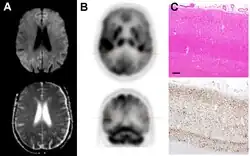

Imaging of the brain may be performed during medical evaluation, both to rule out other causes and to obtain supportive evidence for diagnosis. Imaging findings are variable in their appearance and also variable in sensitivity and specificity.[49] While imaging plays a lesser role in diagnosis of CJD,[50] characteristic findings on brain MRI in some cases may precede onset of clinical manifestations.[51]

Brain MRI is the most useful imaging modality for changes related to CJD. Of the MRI sequences, diffuse-weighted imaging sequences are most sensitive.[52] Characteristic findings are as follows:

Brain FDG PET-CT tends to be markedly abnormal, and is increasingly used in the investigation of dementias.

- Patients with CJD will normally have hypometabolism on FDG PET.[55]